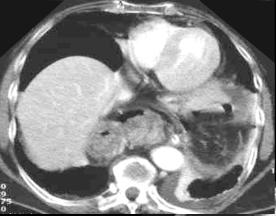

Hernie hiatale de type

I en coupe axiale TDM , fenetre mediastinale .

La poche hydro-aerique gastrique glisse alongee au

dessus hiatus oesophagien en arriere aureillete

gauche et ventricule gauche . |

Meme cas en coupe frontale (

coronale ) .Le cardia et une partie de estoma

situent au dessus le diapragme . Image du

coupe est si nette |

Quelque images en TDM axiale de

hernie hiatale de type II et Type IV :